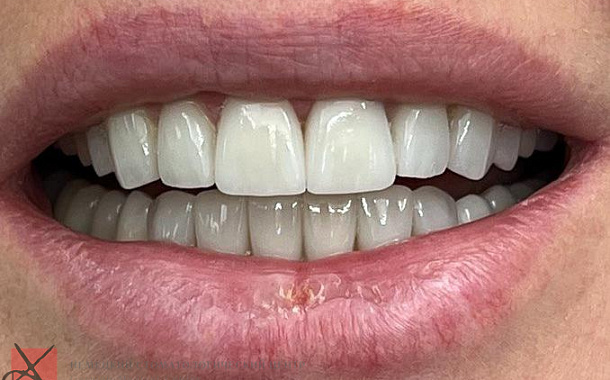

Полный прайс-листКейсы: до и после

Уже на этапе диагностики и планирования лечения зубов мы можем с 99% точностью показать пациенту, как будут выглядеть его зубы после лечения в Немецком Стоматологическом Центре. Наш пациент всегда четко понимает, как будет закрываться его челюсть, как будут выглядеть его зубы, улыбка и лицо после лечения зубов. От нас пациент всегда уходит полностью удовлетворенный лечением и получает именно тот результат, который мы ему показали на первой встрече.